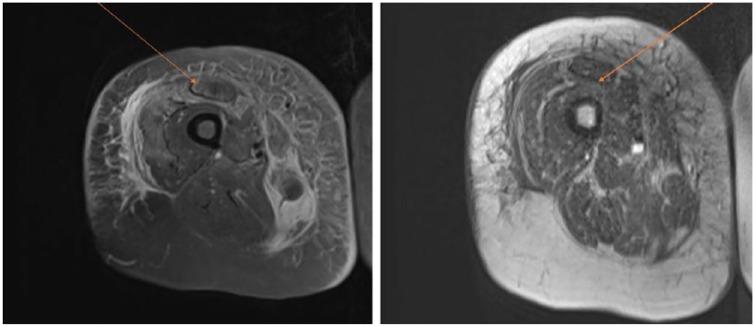

Acquired hemophilia A poses a clinical and diagnostic challenge. Although rare, it is still the most common acquired factor deficiency. We present a case of acquired hemophilia A diagnosed in a 71-year-old female who presented with a right thigh hematoma of acute onset. The diagnosis was established based on the coagulation profile along with factor VIII levels, mixing studies, and inhibitor levels. The patient received multiple lines of therapy including steroids, factor VIIa, Obizur (porcine-derived recombinant factor VIII), followed by multiple cycles of chemotherapy including cyclophosphamide and rituximab.

获得性血友病A带来了临床和诊断方面的挑战。尽管罕见,但它仍是最常见的获得性凝血因子缺乏症。我们报告一例在一名71岁女性中诊断出的获得性血友病A病例,该患者出现急性发作的右大腿血肿。诊断是根据凝血指标以及凝血因子VIII水平、混合试验和抑制物水平确定的。患者接受了多线治疗,包括类固醇、凝血因子VIIa、Obizur(猪源重组凝血因子VIII),随后进行了多个周期的化疗,包括环磷酰胺和利妥昔单抗。